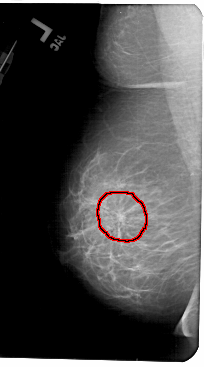

A_1436_1.RIGHT_MLO

FILE: A_1436_1.RIGHT_MLO.OVERLAY

TOTAL_ABNORMALITIES 1

ABNORMALITY 1

LESION_TYPE MASS SHAPE OVAL MARGINS CIRCUMSCRIBED

ASSESSMENT 4

SUBTLETY 5

PATHOLOGY BENIGN

TOTAL_OUTLINES 1

BOUNDARY